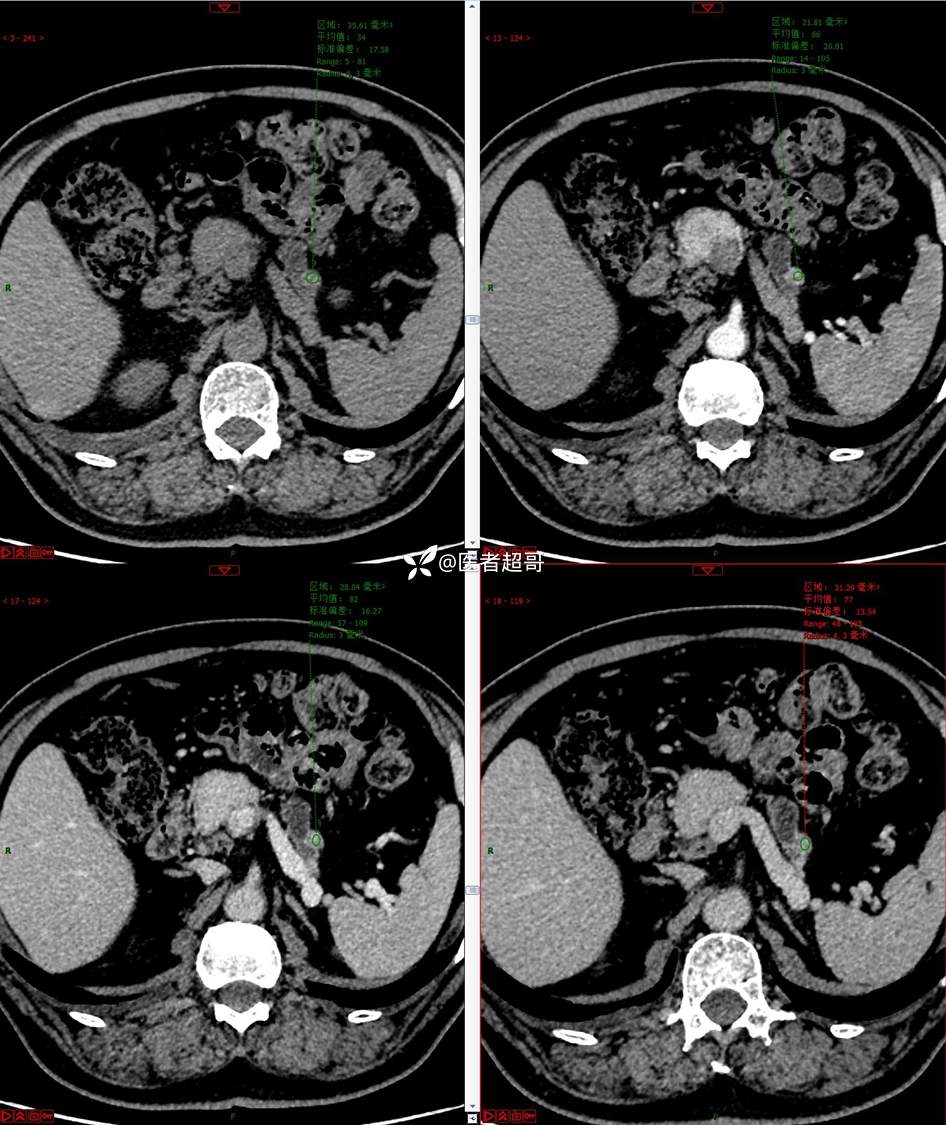

【影诊笔记677】查体发现胰腺占位性病变1周,细节决定成败,请诊断分析!

主 诉:查体发现胰腺占位性病变1周。

现病史:患者1周前在当地查体时发现胰腺占位性病变,无恶心、呕吐,无腹痛,无寒战、高热,无咳嗽、咳痰等异常不适,来我院门诊查上腹部CT平扫+强化:胰腺尾部异常密度灶。今为求进一步治疗,门诊以“胰腺占位性病变”收入院。患者自发病以来,一般情况可,神志清,精神可,普通饮食,二便正常,体重及体力无明显改变。

既往史:既往糖尿病病史2年,口服二甲双胍早晚各一片和格列吡嗪早晚各一片,否认高血压、心脑血管病等疾病史,否认肝炎、结核或其他传染病史及密切接触史,预防接种史不详,否认药物及食物过敏史,否认外伤史,12年前肾癌切除术手术史,否认输血史,其它无特殊。